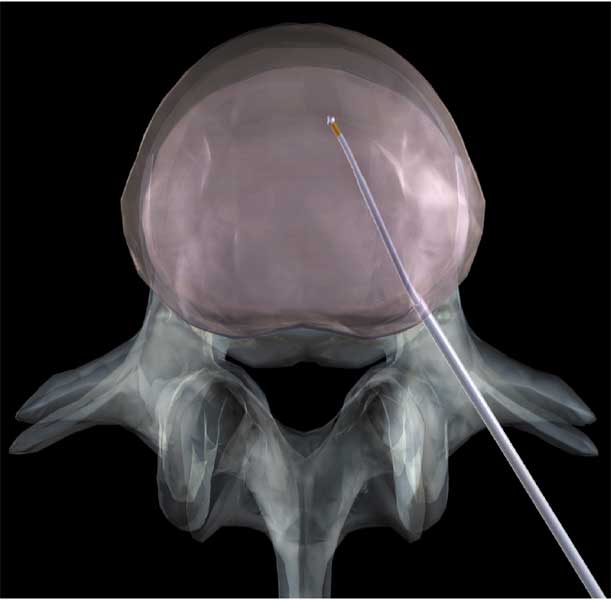

Abb. 1 und 2 von links

Percutaner Zugang zur Bandscheibe

Über die unter Kontrolle des Röntgenbildwandlergerätes eingebrachte wenige Millimeter starke Kanüle erfolgt das Einführen der „Arbeitssonde“. Mithilfe dieser Sonde wird über den sogenannten Coblationseffekt schonend unter geringer Temperaturentwicklung Bandscheibengewebe aus der Bandscheibe entfernt. Die Sonde ist an ihrem Ende leicht gebogen, unter mehrfachem Vor-und Zurückschieben werden mehrere Kanäle in der Bandscheibe geschaffen, hierdurch entsteht ein gewisser Volumeneffekt, eine durch ausgetretenes Bandscheibenmaterial komprimierte Nervenwurzel kann hierdurch wieder frei verlaufen